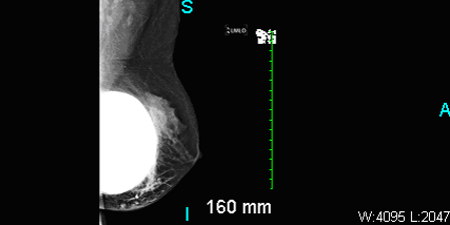

Aside from fever, other vital signs were normal. The patient had bilateral palpable sub-glandular silicone implants with Baker Grade 3 capsular contracture (ie, breast firm to the touch with visible breast deformity) of the right breast. There were no masses and no axillary lymphadenopathy. The right breast was swollen, erythematous, and tender, with an intact inframammary scar. Results of ultrasonography showed no fluid collection or abscess.

Breast augmentation with implants also can make mammography challenging.10 Additional ultrasonographic images are usually needed to detect pathology. But, as seen in this case, implant material may effectively obscure a lesion.

Figure: Ultrasound of right breast showing subglandular implants. No definite abscess seen.